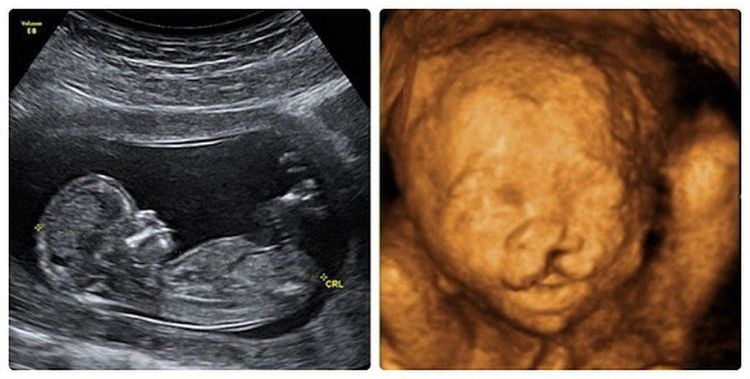

Hiện nay các loại siêu âm rất đa dạng: Siêu âm 2D, 3D, 4D hoặc siêu âm Doppler màu. Do vậy, mẹ bầu có thể lựa chọn tùy ý khi muốn tiến hành siêu âm thai nhi.

Siêu âm 4D cho hình ảnh trẻ chi tiết và chân thực